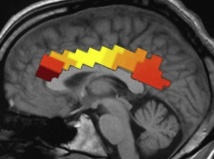

De esta forma, comprobaron que los pequeños con síntomas de autismo más leves presentaban respuestas cerebrales similares a las de los niños con un desarrollo corriente. Esto es, ambos grupos mostraron una respuesta neuronal potente a palabras conocidas en la región parietal temporal del lado izquierdo del cerebro, relacionada con el lenguaje.

Por el contrario, los niños con deficiencias sociales más graves mostraron mayor respuesta neuronal a las palabras en el hemisferio derecho del cerebro, una respuesta que no se ha constatado en niños con un desarrollo corriente y de cualquier edad.

De esta forma, comprobaron que los pequeños con síntomas de autismo más leves presentaban respuestas cerebrales similares a las de los niños con un desarrollo corriente. Esto es, ambos grupos mostraron una respuesta neuronal potente a palabras conocidas en la región parietal temporal del lado izquierdo del cerebro, relacionada con el lenguaje.

Por el contrario, los niños con deficiencias sociales más graves mostraron mayor respuesta neuronal a las palabras en el hemisferio derecho del cerebro, una respuesta que no se ha constatado en niños con un desarrollo corriente y de cualquier edad.